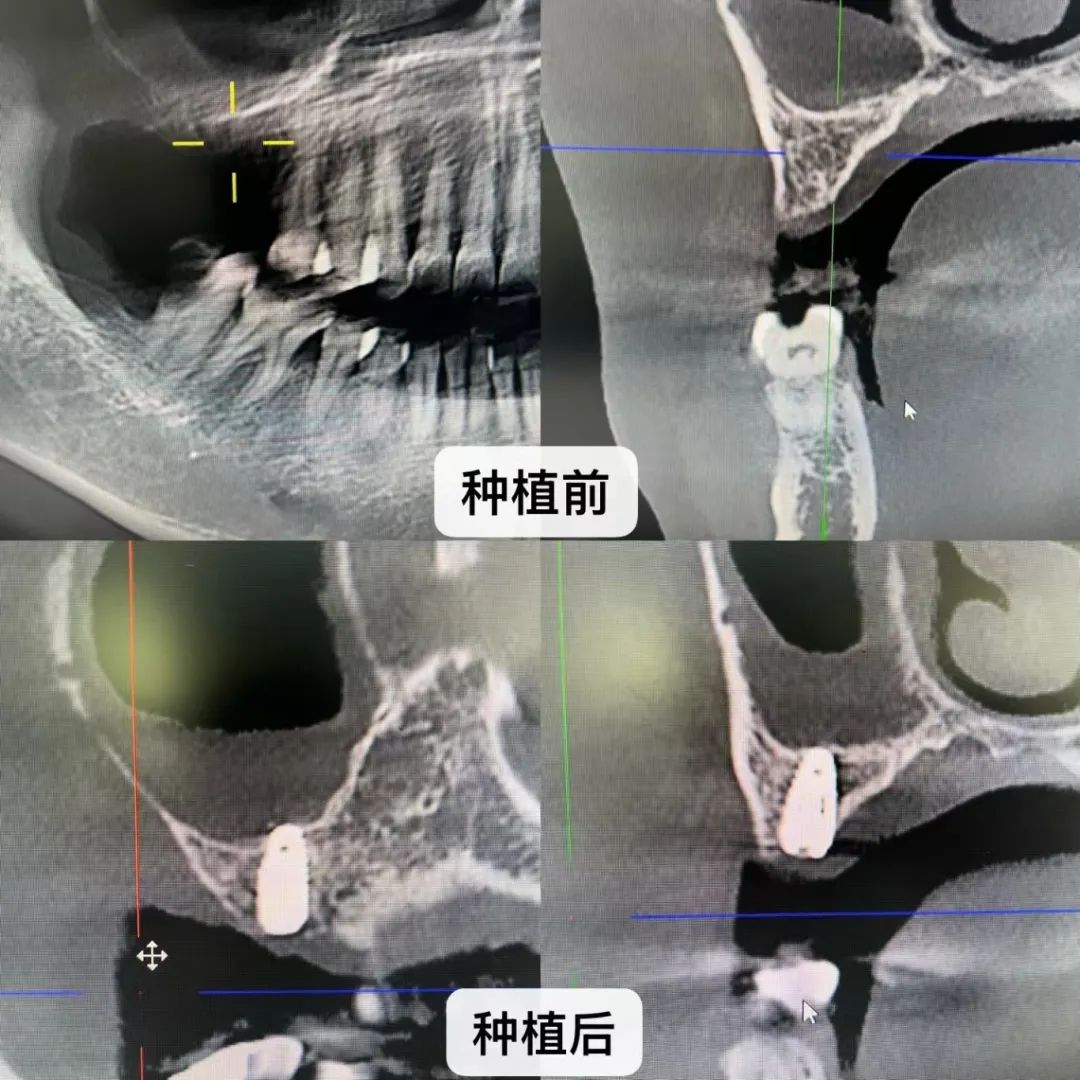

在寻求专业医疗意见后,温女士得知由于长时间的牙齿缺失,她的牙槽骨发生了显著性的吸收,并且右侧上颌窦长期积聚液体,这正是导致她出现异常“流鼻涕”症状的根源所在。医生进一步建议,为了改善这一状况,需要进行一系列复杂且精细的手术,包括“上颌窦提升术”与“植骨手术”。面对这一系列繁琐且可能伴随风险的治疗方案,温女士不禁心生怯意,犹豫不决。

不久前,温女士通过朋友圈的一条信息得知,市中医医院有口腔领域的专家免费坐诊,于是,满怀期待与希望的温女士一大早便匆匆赶往医院,渴望能找到解决问题的良策。省口腔领域的知名专家张特教授与市中医医院口腔科主任刘琴文,在经过全面而细致的面诊后,告知温女士,无需进行上颌窦提升术,也无需进行植骨手术,整个手术时间预计仅需大约三十分钟!这一突如其来的喜讯让温女士激动不已,她随即表达了立即接受手术治疗的强烈愿望。

术中,刘琴文主任在张特教授的指导下成功通过温女士上颌窦底骨皮质,将4.1*8mm植体完美植入,达到双皮质骨固位,稳定性非常好,并且鼓气时也没有上颌窦黏膜穿孔的情况发生。成功解决了温女士长期以来的缺牙困扰。